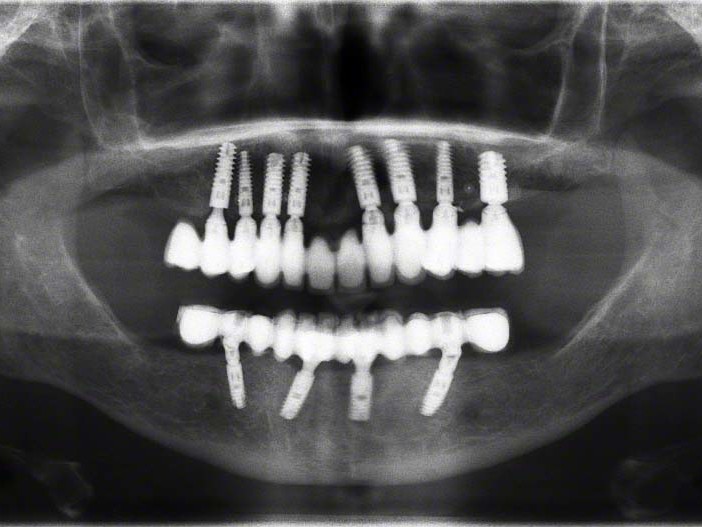

Bei dem nachfolgenden Fall handelt es sich um eine 74-jährige Patientin, die nicht raucht sowie im guten Allgemein- und Ernährungszustand ist. Sie steht in keiner medikamentösen Behandlung und hat keine Allergien. Erstmals kam die Patientin 2006 in die Behandlung der Autoren. Damals zeigte diese eine insuffiziente Teleskoparbeit im Oberkiefer, wobei die Pfeilerzähne einen deutlichen Lockerungsgrad aufwiesen. 2006 wurde der Oberkiefer mit acht Ankylos® Plus Implantaten (Dentsply Implants, Mannheim) und einer Sofortversorgung bei gleichzeitig durchgeführtem Sinuslift rehabilitiert. Acht Monate später erfolgte die endgültige prothetische Versorgung in Form einer festen Verblendkeramikauf NEM-Gerüst unter Verwendung von Titan-Abutments. Seit dieser Behandlung ist die Patientin in einem regelmäßigen Prophylaxe-Programm eingebunden und zeigt eine sehr gute Mundhygiene. Die seinerzeit belassene Unterkieferprothetik war mittlerweile insuffizient. Es konnten im Unterkiefer keine Zähne erhalten werden. Seitens der Patientin bestand der Wunsch nach hochwertiger Rehabilitation des Unterkiefers möglichst mit einer Sofortversorgung. Eine zwischenzeitliche Versorgung mit einer gingivagetragenen Interimsprothese schied aus. Darüber hinaus war für die Patientin wichtig, eine möglichst geringe Belastung durch die anstehende Behandlung zu erfahren. Es fiel die Wahl auf die prothetische Lösung mit anguliert gesetzten Ankylos® C/X-Implantaten nach dem SmartFix-Konzept (Dentsply Implants, Mannheim), ein implantatprothetisches Verfahren zur Sofortversorgung von zahnlosen Patienten mit verschraubten Brücken im Unterkiefer. Die Patientin wurde mit einem computerdesignten Langzeitprovisorium über 4 Monate versorgt (Abb. 1).

Wie weiter oben bereits beschrieben ist die Patientin im Oberkiefer mit einer keramisch verblendeten implantatgetragenen Brücke versorgt. Aus Sicht des Behandlungsteams schied daher eine keramische Verblendung des Unterkiefers aus. Die Verwendung von einem Composite mit keramischer Füllstruktur gewährleistet neben der notwendigen Farbstabilität und Plaqueresistenz zwei weitere Vorteile. Auf der einen Seite entsteht im Okklusionsmoment nicht das „keramische Klacken“ und zum anderen werden die auftretenden Kaukräfte gleichmäßiger auf das Implantat und den Knochen verteilt . Gerade bei implantologischen Oberkiefer- und Unterkieferversorgungen ist dieser „Stoßdämpfer–Effekt“ für den Langzeiterfolg wichtig. In dem vorliegenden Fall wurde die okklusal verschraubte Brücke aus einem massiven Titanblock gefräst (Abb. 4 und 5), wodurch das Endprodukt frei von aus der Gusstechnik bekannten Lunkern oder Verzügen ist. In Übereinstimmung mit den als Sheffield-Test ⁷ bekannten Kriterien der University of Sheffield, GB. ermöglicht dieser Fertigungsprozess gepaart mit der verblockten Abdrucknahme einen präzisen und somit spannungsfreien Sitz der Brücke – sowohl auf dem Meistermodell als auch im Munde des Patienten. Sowohl die Verblendungen der Zähne als auch des Zahnfleisches wurden unter Zuhilfenahme der diagnostischen Aufstellung mit visio.lign ⁸ im Labor angefertigt. Hierbei wurde besonderer Wert auf die naturgetreue Nachbildung der Rot-Weiß-Ästhetik und eine gute Hygienefähigkeit gelegt. Die Vorteile dieses Verblendsystems liegen in der exakten Umsetzung von der Aufstellung hin zur fertigen Arbeit durch mehrschichtige Verblendschalen (Abb. 6). Diese Verblendschalen werden schon bei der diagnostischen Aufstellung individualisiert und nach der Gerüstfertigstellung weiterverarbeitet. Mit passenden Individualisierungs- und Ergänzungsmassen sowie einem farblich abgestimmten Verbundsystem mit sehr guter Druck-Scheer-Festigkeit ⁹ ermöglicht dieses System durch Hinterlegen mit Intensivfarben das Gestalten von Mamelons ebenso wie die individuelle Gestaltung von Dentinleisten. (Abb. 7 und 8). Nach der zahntechnischen Erstellung der Unterkieferbrücke wurde diese intraoral inkorporiert (Abb. 9a). Die Implantatschrauben wurden mit 25 Ncm angezogen. Ein wichtiger Hinweis ist, dass hier stets das Originalequipment des Herstellers oder ein elektronisch kalibrierter Schraubendreher seine Anwendung finden sollte. Die Schraubenkamine wurden initial mit einem bakteriendichten, formstabilen lichthärtenden temporären Füllungsmaterial ¹⁰ verschlossen (Abb. 9b). Nach 6 Wochen werden die Implantatschrauben seitens des Prothetikers nochmals kontrolliert und ein abschließendes OPG erstellt (Abb. 10).